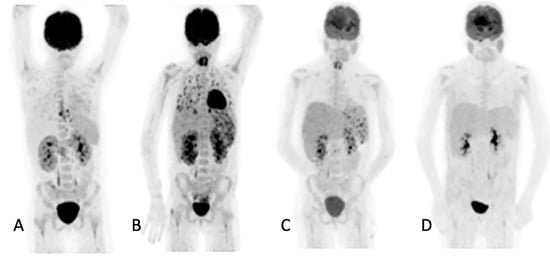

Of the 155 [18F]FDG PET/CT studies that were analyzed, 34 (22%) had no anatomy-based imaging (Table 3). Of the 34 [18F]FDG PET/CT studies that had no anatomy-based imaging, 28 (82.4%), were scans that were performed for the follow-up of IFI lesions that had been previously noted by previous imaging. The remaining four were two in patients being prepared for ASCT, and two in two patients for which [18F]FDG PET/CT had found metabolic activity in residual IFI lesions. Figure 2 shows a patient for which [18F]FDG PET/CT only was used to follow up because the IFI lesions could only be detected by the metabolic component of the study. Table 3 outlines the number of anatomy-based studies that were performed for each [18F]FDG PET/CT scan studied and the concordance between the [18F]FDG PET/CT and anatomy-based study at the site of the study.

Figure 2. Maximum intensity projection (MIP) of [18F]FDG images of a 10-year-old girl on chemotherapy for acute lymphocytic leukemia. She had a persistent fever unresponsive to antibiotics. HR CT not shown (was unremarkable). The initial study (A) revealed widespread, multiple, small, metabolically active foci in the muscles and esophagitis, which were later found to be due to Candida dubliniesis upon biopsy. The lesions were not detected by the corresponding CT of the [18F]FDG PET/CT study. A follow-up [18F]FDGPET/CT study (B) after 6 weeks of antifungal treatment showed a very good metabolic response, with a single residual focus in the right gluteus and the resolution of the esophagitis. No anatomy-based study was performed together with the follow-up [18F]FDG PET/CT study (B).